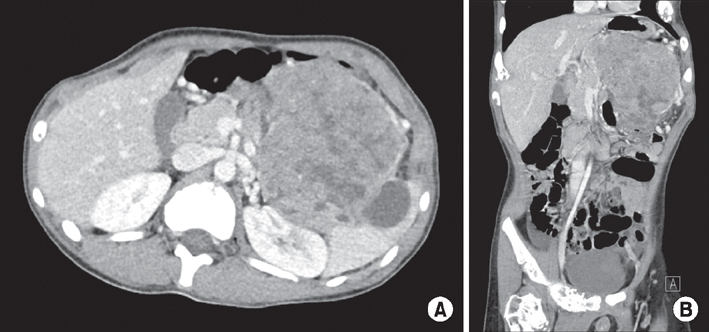

The patient started a standard diet 9 days postoperatively and was discharged the following day. Pathological diagnosis of the tumor determined a mitotic count of 50 cells/10 HPF; 30% of the tissue was necrotic, and the tumor cells were positive for chromogranin A and synaptophysin, which supported the final diagnosis. Ki-67 proliferative staining was positive in 80% of cells, and the tumor cells were positive for beta-catenin, CD10, E-cadherin, and cytokeratin (

Fig. 2,

3). The final pathological diagnosis was mixed acinar-endocrine carcinoma. The patient is currently undergoing adjuvant chemotherapy with cisplatin, etoposide, and cyclophosphamide in our pediatrics department; the regimen of chemotherapeutic agents used was based on the standard regimen used to treat pancreatoblastoma.

Fig. 2(A) Surgical pathology of an abdominal mass in the pancreatic body and tail, presenting with an infiltrative tumor border, 30% necrosis, and a mitotic count of 50 cells/10 HPF (H&E, ×100). (B) Electromagnetic study of the pancreatic body and tail. Some tumor cells show cytoplasmic fat vacuoles or neurosecretory granules suggesting predominantly endocrine differentiation.